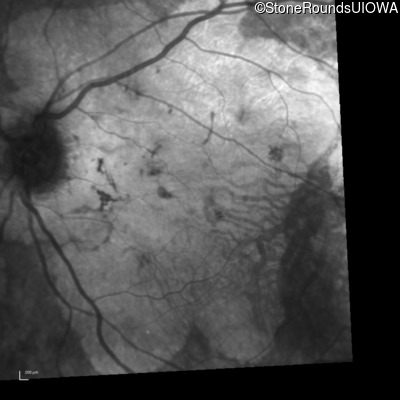

Infrared Fundus Photograph - Right - 20/100 +1

Exemplar